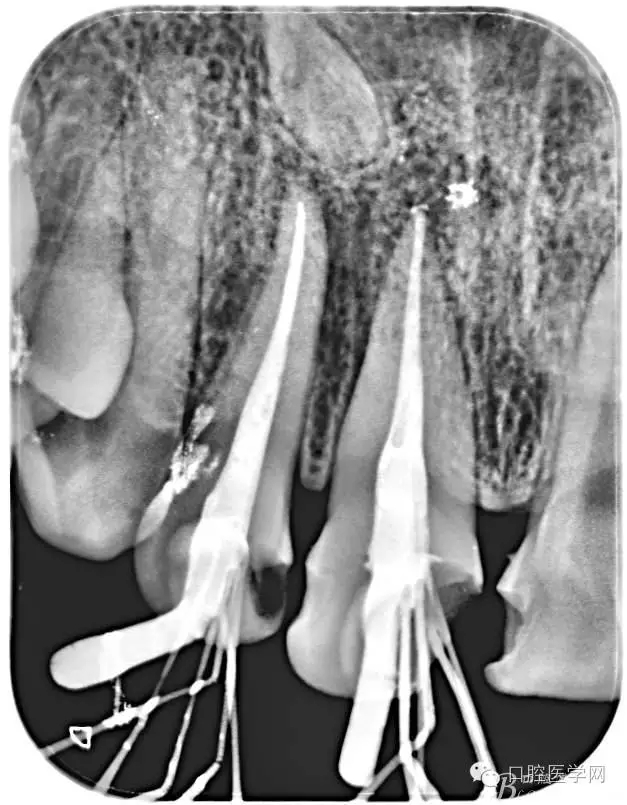

根管的解剖界限是从髓室根管入口到根尖部牙本质- 牙骨质交界处(生理性根尖孔) 。理想的根管充填应该是对生理性根尖孔冠方以上进行严密的三维封闭。临床上根据X线牙片判断根管充填的质量。牙片上充填材料与根管壁紧密接触一般被认为充填严密。关于充填止点,由于牙本质- 牙骨质界离根尖孔外表面平均距离为0. 5~0. 7 mm,同时相当多的根尖开口并不位于X线片的根尖处。因此临床上认为材料充填至距X线片牙根最尖端0. 5~1 mm (也有认为0. 5~2mm)为适填。

为达到更为理想的根充效果,研究人员和牙髓病医生一直在探索根管充填技术,并且发展出多种可供选择的方法。Ingle]将其归纳为3 类: ①“牙胶尖+封闭剂”式; ②“根尖1 /3充填”式; ③“注射或螺旋充填”式。目前临床广泛采用的主要是“牙胶尖+封闭剂”方式。按照充填压力的方向(侧向或垂直)不同和牙胶温度(冷或热)不同,根管充填有2 种基本技术:冷牙胶侧方加压充填和热牙胶垂直加压充填。现有的各种充填方法均是这2 种基本方法基础上的发展或改良。医生可根据方法的优缺点以及个人习惯选择使用。

6、封闭剂使用